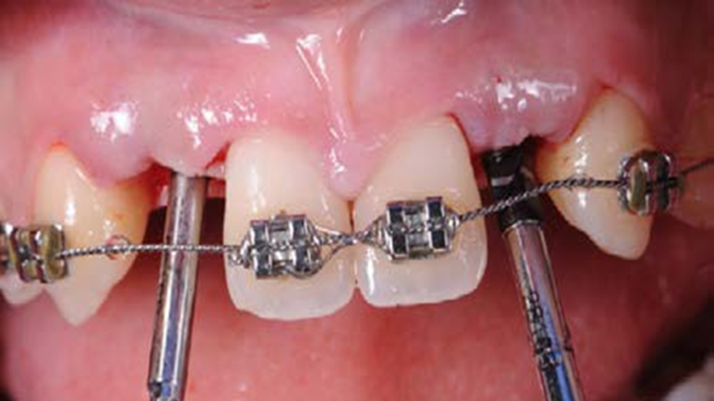

Clinical case: BPET PREDICTABILITY - State-of-the-Art SOCKET SHIELD

- Courtesy of Dr. Howard Gluckman, South Africa -

“AnyRidge is perfect for the anterior esthetic zone due to its strong initial stability & fast osseointegration.

Plus, KnifeThread® ensures space maintenance when using the PET/Socket Shield/Root Membrane Technique, showing excellent bone growth.”